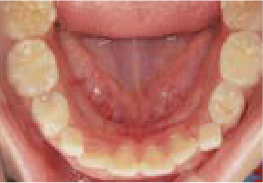

現役歯科医師の愛娘さんの治療

Nさん (矯正開始時:8歳)

Before

After

上あごの成長が少なく、特に前歯のガタガタが目立っていました。口呼吸のクセや飲み込み方に良くないクセが確認されました。

治療を終えて

マイオブレイスとBB1装置で上あごの成長を助け、鼻呼吸や正しい飲み込み方を身につけることで、きれいな歯並びとしっかり噛めるお口に変わっていきました。

姿勢やお口の機能を正しく整えたので、後戻りしない綺麗な歯並びを維持できています。もちろん非抜歯です。

主訴・治療内容 当院と交流のある歯科医師の先生が、ご自身のお子さまの治療を任せてくださいました。

「難しい歯並びでも永久歯を抜かず、全身の健康と顔立ちも考えて治療してくれる」と信頼していただいて治療開始。

治療期間 3年

費用 462,000円(税込)